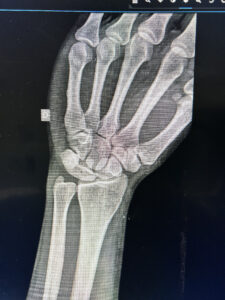

A alteração representada na radiografia é:

ADoença de Kienbock

BBraquimetatarsia

CCoalizão carpal

DRizartrose